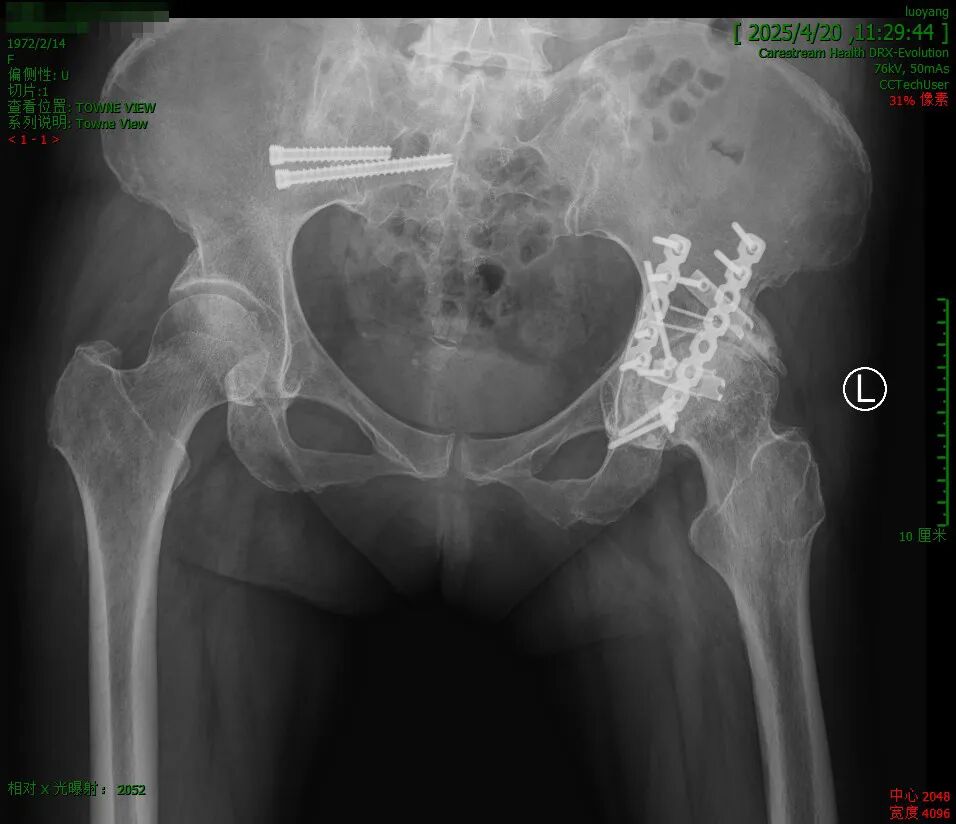

W女士,13年前因髋臼骨折行内固定手术,近2年来左髋部间断疼痛并活动受限、跛行,拟行人工髋关节置换术。

密密麻麻的钉子: